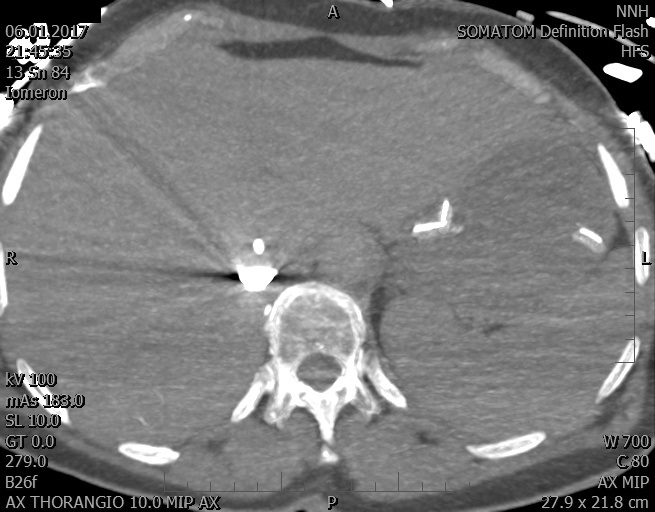

Video 2 - Echokardiograficky byla zjištěna těžká dysfunkce dilatační levé komory s nezvětšenou pravou komorou.Pro nejasnou příčinu zástavy jsme provedli i vyšetření výpočetní tomografií (CT), které vyloučilo plicní embolizaci (série 1 - soubory na konci článku). V den přijetí při přetrvávající oběhové nestabilitě byla nemocná opakovaně defibrilována pro fibrilaci komor se stabilizací rytmu po podání amiodaronu a mesocainu. Dle hemodynamických měření se jednalo o těžký kombinovaný šok. Vstupní laboratorní vyšetření bylo bez větších pozoruhodností. Posléze jsme doplnili anamnézu od příbuzných a zjistili, že pacientka užila do dvou hodin před srdeční zástavou první tabletu amoxicilinu na lehký respirační infekt. Při nevýtěžnosti vstupních vyšetření a nových anamnestických informacích jsme doplnili 14 hodin po kolapsu vyšetření koncentrace tryptázy v séru, která byla extrémně zvýšena (tabulka 2), což nás vedlo k podezření na anafylaxi.